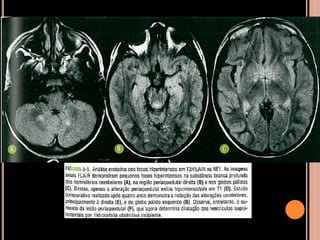

Área de vacuolização de mielina

 Focos hiperintensos em T2 e no FLAIR em núcleos

da base, cápsula interna, tronco encefálico e

cerebelo;

 Mais comum no globo pálido, geralmente bilateral;

Vacuolização de mielina

 Aparecimento geralmente aos 3 anos  aumenta

até os 12 anos  tendência a regredir;

 Raro observar após os 20 anos de idade;